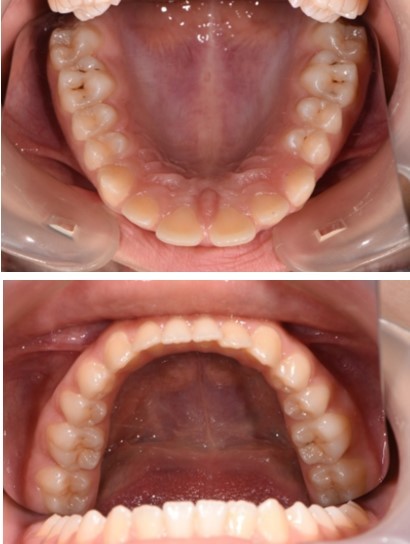

In order to emphasize one of the major indications of skeletal anchorage with mini implants, a clinical case was selected. A young teenage patient (Figure 1, Figure 2, Figure 3, Figure 4), with a severe overjet, flared upper incisors with spacingand a convex profile was reffered to our dental office. Treatment objectives were established from the beggining: retrusion of the upper anterior teeth, overjet and overbite correction, space closure and obtaining a better occlusion. Anchorage needs were evaluated. Absolute anchorage was needed in order to obtain upper dental retrusion without mesial movement of the posterior teeth. Two mini implants were placed bilaterally, in a labial position, between the second premolars and upper first molars. Both mini plates and mini implants provide a predictable result in this case but since mini implants are more easy to place and provide a higher degree of comfort, this option seemed more suitable. In this way, the need for other anchorage devices, such as a palatal arch or headgear was eliminated. The upper incisors and canines can be now distalized and intruded, after the upper premolar extraction.

Figure 4.Treatment start - Orthodontic appliance on the upper arch, Roth 022" prescription.

Treatment started with orthodontic appliances on the upper arch, Roth 022" prescription. In order to achieve a better retraction of the upper teeth, first bicuspids were extracted. Retraction of the upper incisors with elastics chains placed from crimpable hooks to orthodontic implants.